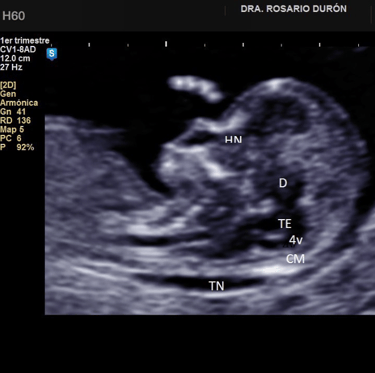

Diagnóstico prenatal avanzado

Mediante técnicas como la ecografía genética, la medición de la translucencia nucal y la cardiotocografía para detectar anomalías.